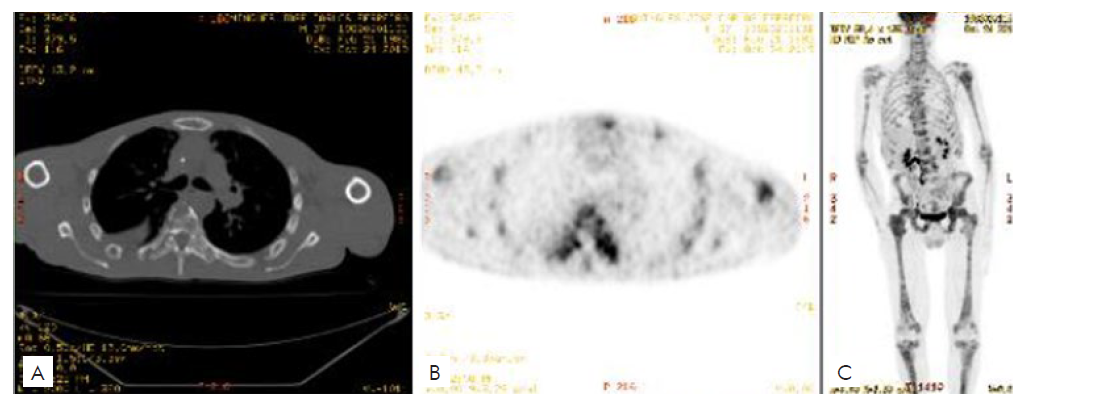

The restaging 18F-fluorodeoxyglucose (18F-FDG) PET-CT showed extensive lytic bone metastases.

PET-CT performed in June 2019 revealed diffuse spreading bone metastases, the appearance of new cutaneous and subcutaneous metastases in the frontal region, and bilateral pulmonary micronodulation. The patient was then recommended to for a second line of chemotherapy with carboplatin and paclitaxel. However, in October 2019, PET-CT noticed the massive progression of bone and lung metastases (Fig. 3), and so it was decided to do a therapeutic switch to itraconazole (800 mg, once daily), discontinued three months later, due to poor response and adverse events, mainly fatigue.